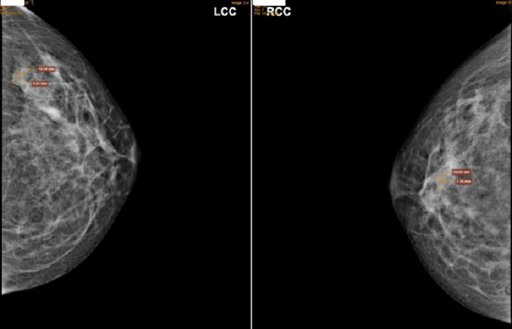

Người phụ nữ mắc hai tổn thương khác nhau ở hai bên vú

Người phụ nữ phát hiện có nhân bất thường ở hai bên vú nên đến Bệnh viện Đa khoa MEDLATEC khám. Tại đây, người này được xác định mắc hai tổn thương khác nhau là u xơ tuyến vú và quá sản ống thông thường ở hai bên vú.